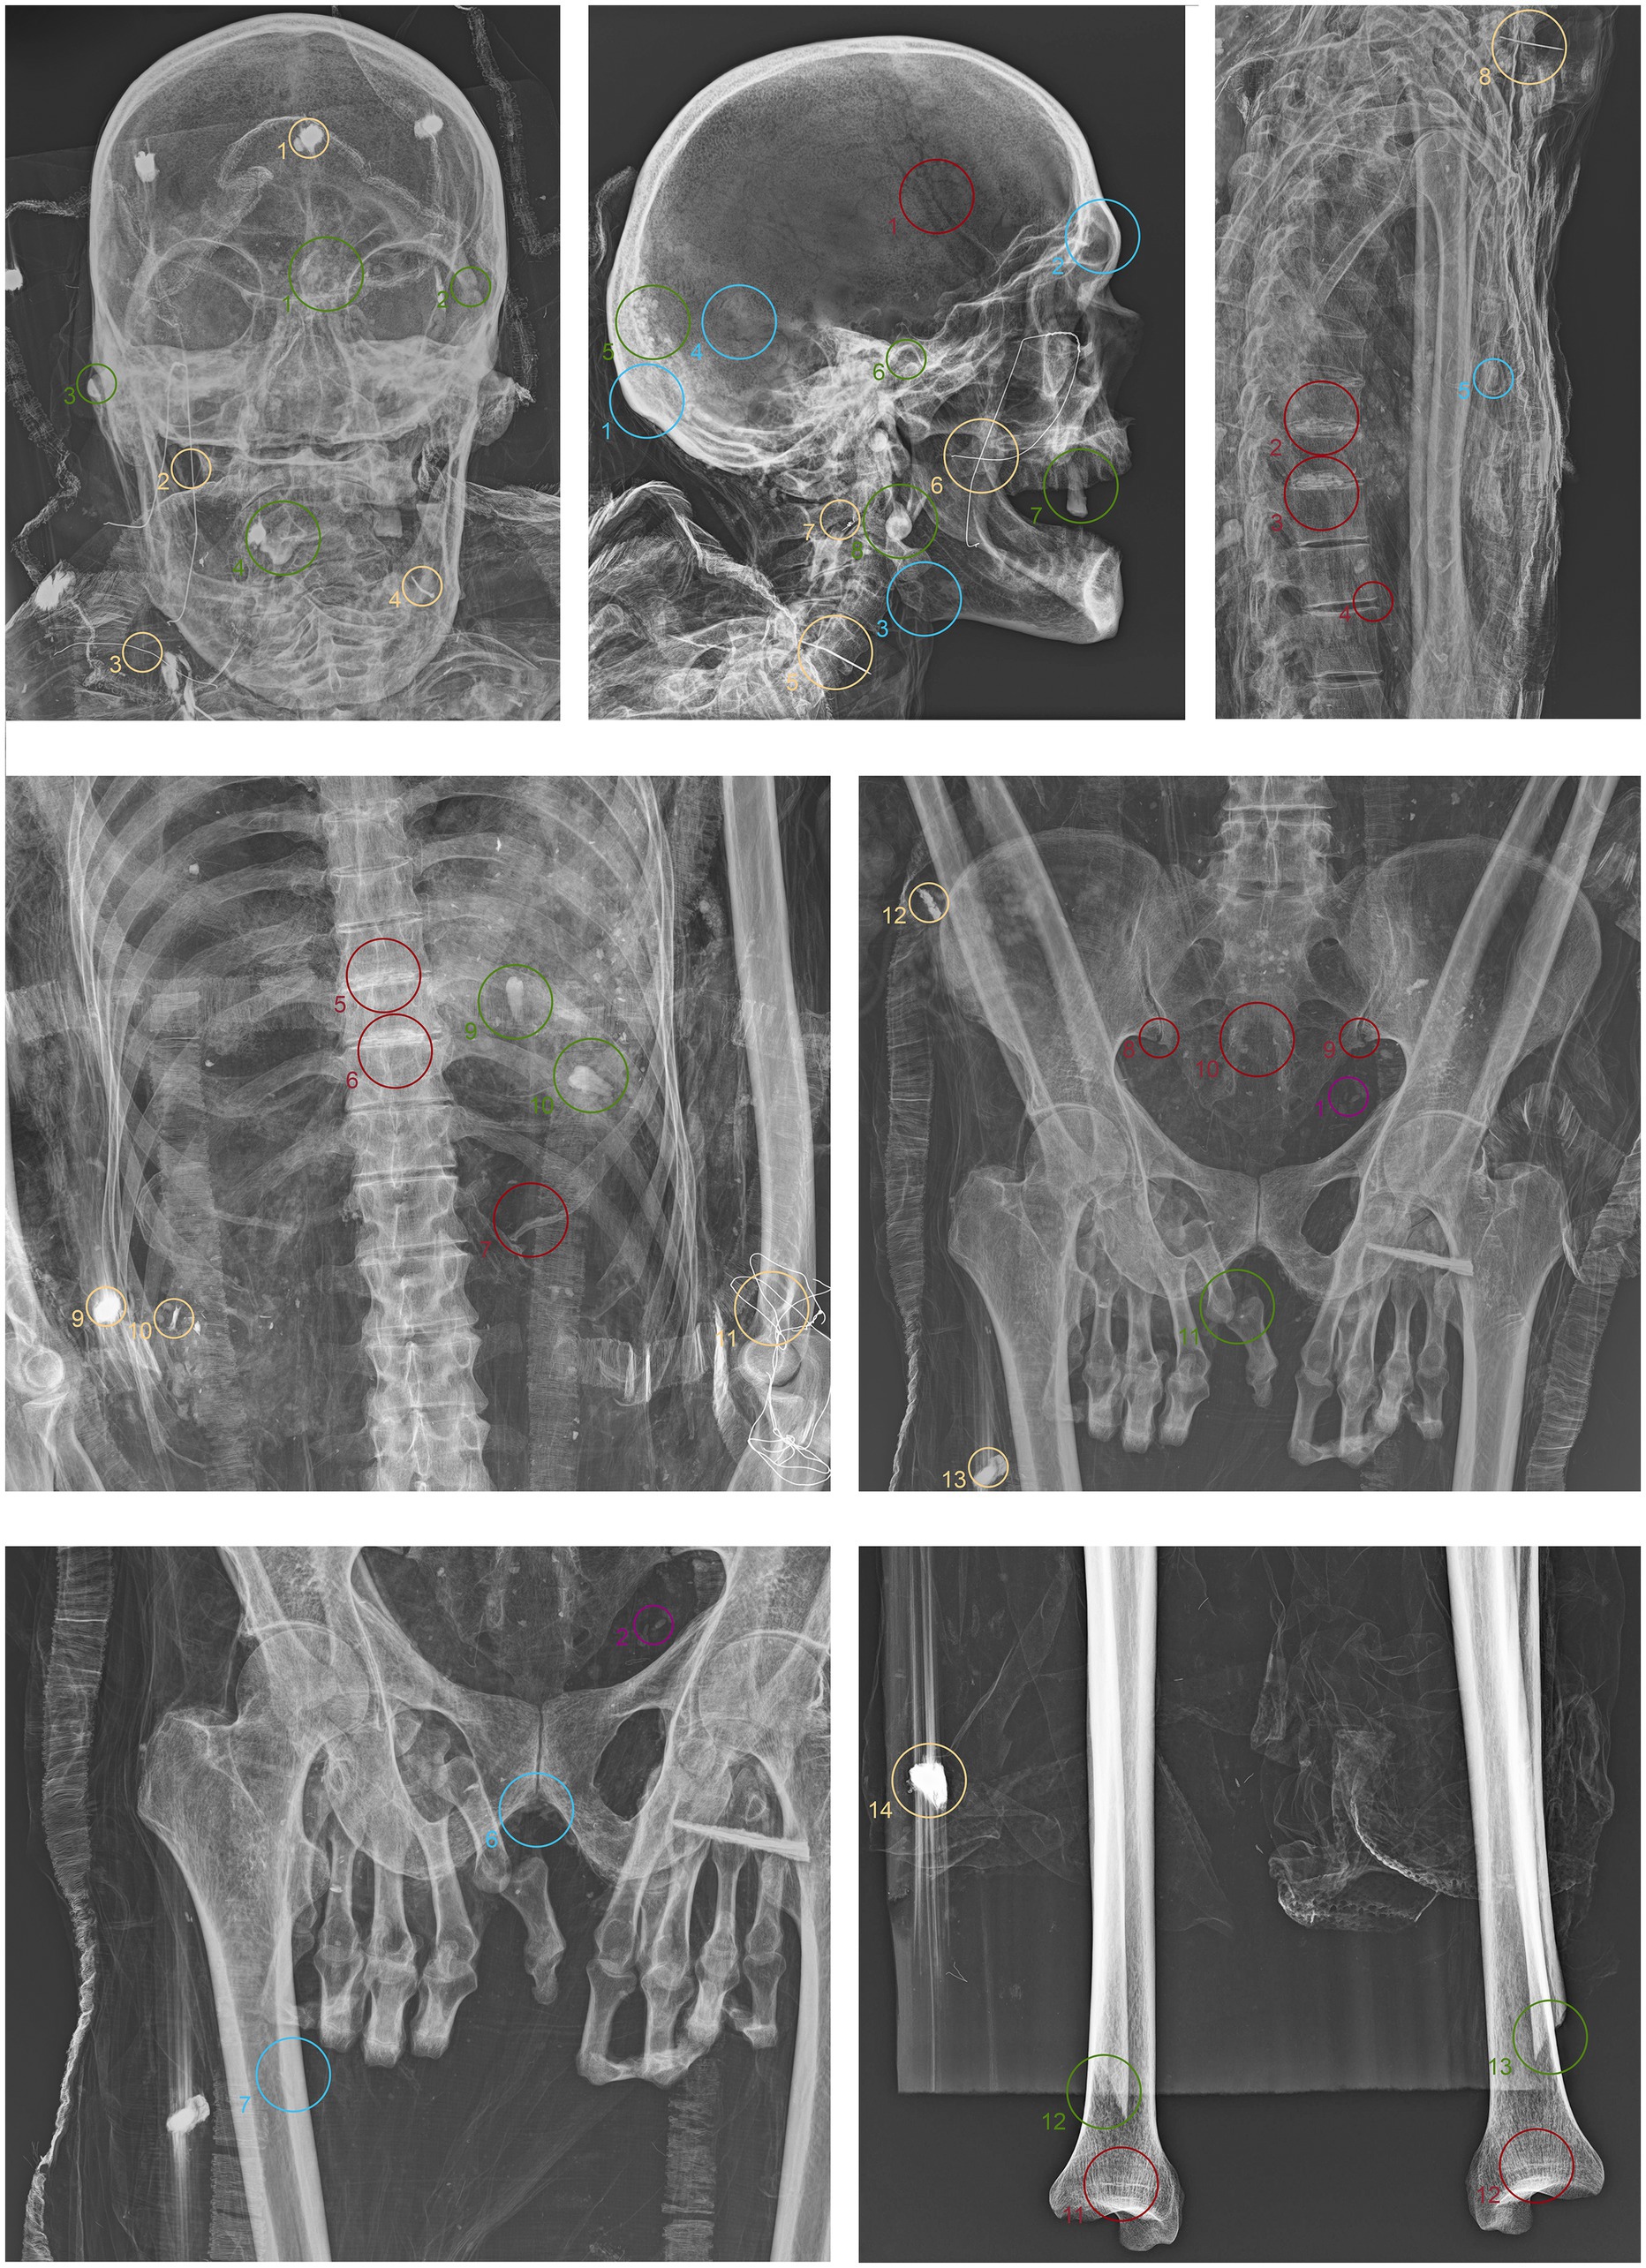

ID3. As in the previous subjects, fine material is observed within the occipital region of the neurocranium (Figure 7.1 green). The hyoid bone is visible in its anatomical position (Figure 7.2 green). The upper spine remains in perfect anatomical alignment. However, there is a discontinuity between the first and second thoracic vertebrae, with the upper segment displaced anteriorly by approximately 4 cm in the sagittal plane (Figure 7.3,4 green). A bone fragment and the distal portion of the right fibula are recognized as fragmented at the level of the mid-diaphysis of the right femur (Figure 7.5,6 green).

Figure 7. Anteroposterior and lateral radiographic acquisitions of the individual ID3. Green highlights indicate areas of interest for taphonomic study, yellow highlights indicate areas relevant to the assessment of restorations predating this study, violet is used for entomological analysis, blue for anthropological aspects, and red for paleopathological evidence.

ID3. In this individual, numerous nail used for the mummy supports are visible (Figure 7.1,6,8,11 yellow). In this case, one image highlights the more radiodense halo that characterizes many of the metallic elements of the supports (Figure 7.10 yellow). Several small pins with heads are positioned in the upper part of the subject (Figure 7.2,3,5 yellow), while iron wire binds the right wrist and hand, with loops extending to bind individual fingers (Figure 7.7,9 yellow).

ID3. In both anteroposterior and lateral views, the sagittal suture and lambda are unfused (Figure 7.1,2 blue). The subject has a prominent gonion of the mandible, a mandibular angle near 90°, and a very pronounced glabella (Figure 7.3,4 blue). The presence of the right lower third molar is also evident, while the other three third molars are absent (Figure 7.5 blue). While the bones have fused, the manubrium and first sternebra remain separate, and fusion lines on the proximal ends of the fibulae and tibiae are still evident (Figure 7.6, 8–10 blue). The pelvis is robust, with a subpubic angle of approximately 90°, although the left hemipelvis is slightly rotated counterclockwise (Figure 7.7 blue).

ID3. The lateral projection of the skull highlights the morphology of the pulp chamber of the left second lower molar, which exhibits a “chair-shaped” configuration (Figure 7.1 red). The 8th thoracic vertebra is compressed in the anterior view, accompanied by a milder compression of the 7th vertebra. This condition is associated with osteophytes along the margins of both vertebral bodies, as well as the preceding and following vertebrae (Figure 7.2,3 red). Additionally, the vertebral endplates, which are slightly sclerotic, show small areas of erosion in the central portion (Figure 7.4,5 red). In this individual, the insertions of the oblique muscles on the iliac crest also show significant alterations in this region (Figure 7.6 red).